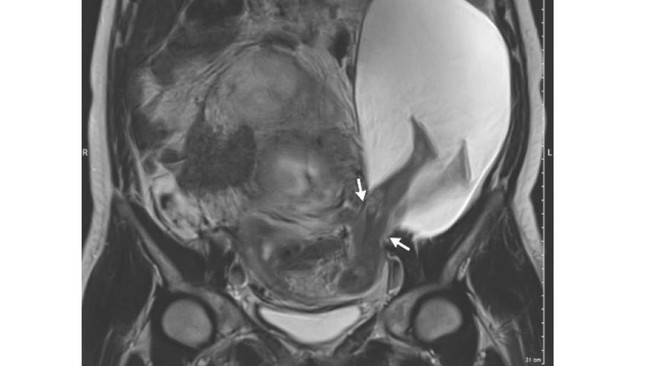

O al menos fue entonces cuando lo vieron. En la semana 22 se realizó una ecografía de rutina y vieron que algo no iba bien. Entonces le hicieron una resonancia magnética que reveló lo que veis en la imagen de arriba: las piernas del bebé habían salido del útero, y con ellas parte del saco y del líquido amniótico. La apertura medía unos 2,5 cm y a través de ella se habían colado sus piernas y las otras estructuras.

Finalmente, en la semana 30 se hizo una nueva ecografía que reveló que la apertura medía ya 5 cm y que la parte del saco que estaba fuera del útero había crecido de tamaño aún más. Entonces se realizó la que sería la sexta cesárea de la mujer, que dio como resultado el nacimiento de un bebé varón sano que pesó 1,385 Kg.